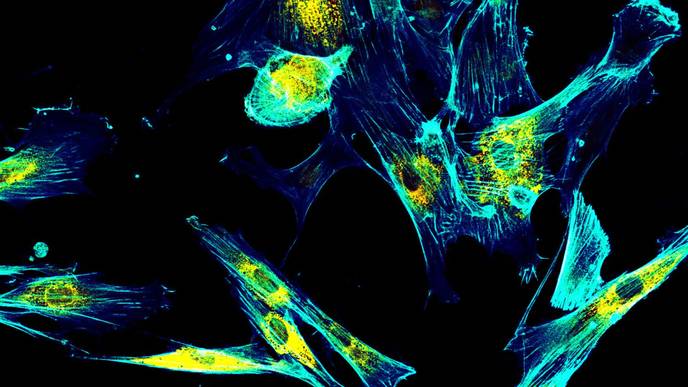

Fibroblasts make collagen, a protein that gives the skin structure and strength. In previous research, Weeraratna and colleagues showed that age-related changes in fibroblasts promote the spread of melanoma tumor cells and lead to worse outcomes. Now, they confirm that fibroblasts age differently in men and women, and the age-related changes that occur in male fibroblasts contribute to more aggressive, hard-to-treat melanomas.

In experiments comparing aged human male and female fibroblasts, they discovered that the male fibroblasts accumulated reactive oxygen species that stress and damage cells. They also found that the aged male fibroblasts produce higher levels of bone morphogenic protein 2 (BMP2), a protein usually involved in development of bone and cartilage.